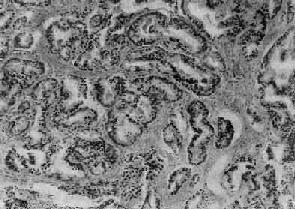

镜下,97%的前列腺均为腺,少数为移行细胞和鳞状细胞。依其分化程度可分为高分化、中分化和低分化3型。高分化前列腺最多见,细胞排列成大小不等的腺样结构,颇似前列腺增生腺体,但细胞体积较小,核较深染,上皮细胞往往呈多层排列并较不规则(图14-4),有时可呈乳头状腺或腺泡腺结构,并常可见组织向间质浸润生长;中分化腺全部或部分呈腺样结构,但腺体排列较紊乱,核异型性较明显,且有时形成筛状结构;低分化腺细胞一般较小,排列成实体团块或条索,腺腔样结构很少(图14-5)。多数病例乃由上述多种组织结构混合组成。

图14-5 前列腺(低分化型)

细胞异型明显,并呈筛状结构